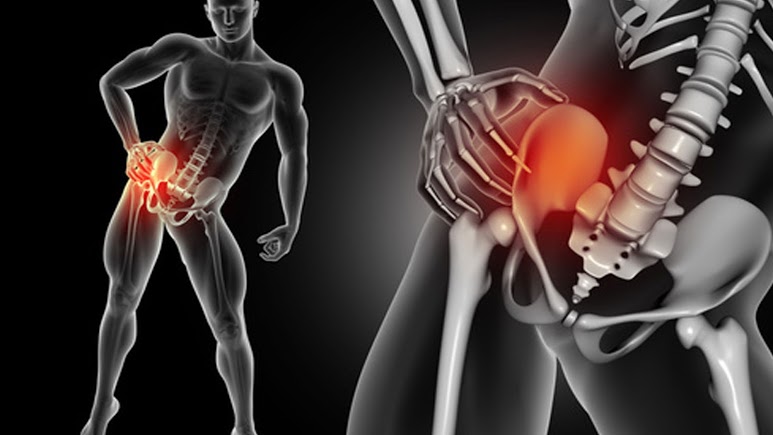

Hip Flexor Treatment For Painful Back Hips and Legs

There are some common reasons that they are left out. The hip flexors muscles are the psoas and the iliacus.

Treating Hip Flexor Pain At Home With Exercise and Stretching Methods